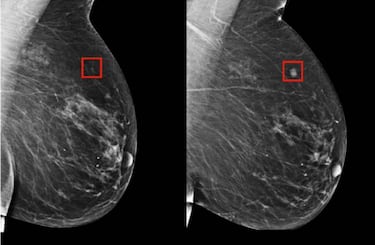

Resulta que en Instituto de Tecnología de Massachusetts, conocido por otros proyectos como el dron que vuela sin hélices, ha desarrollado una nueva IA capaz de reconocer un cáncer de mama. Pero la mejor característica es su capacidad de predicción, y es que el algoritmo es capaz de reconocerlo incluso cinco años antes de que ocurra. Para ello, el software se ha entrenado con cerca de 90.000 mamografías con las que es capaz de encontrar patrones solo perceptibles de una forma muy detallada. Solo queda esperar que algún día esta tecnología se implante en los hospitales y salve muchas vidas.